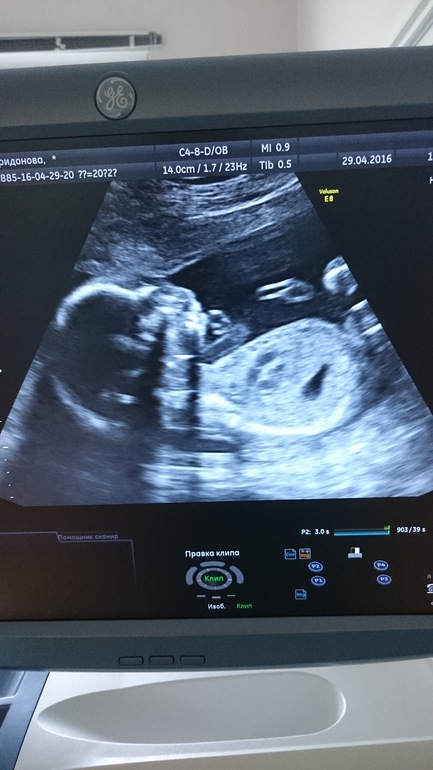

Так я ждала этот день, что и волноваться забыла) Волнение меня настигло только в момент, когда я села в коридоре возле двери с надписью УЗИ) Напротив меня весел шикарный яркий стенд под названием "Причины патологии плода" ... Нда... Я ознакомилась с этой "чудесной" напутственой статей и на дрожащих ногах зашла в кабинет) Дальше были пять минут ничего не говорящих мне аббревиатур и цифр, которые озвучивала врач...каждый раз, когда она напряженно замирала и всматривалась в монитор, я прощалась с жизнью и переставала дышать) Потом стало понятнее, началось перечисление внутренних органов. И как-то совсем между прочим.. прозвучали слова: у вас тут девочка!) Теперь нет сомнений! Ещё одна лапочка-дочка! Крашу кружочек со спокойной душой))) Все показатели у нас в норме, к счастью! Срок поставили 20-21 неделя. Расти, доченька, здоровой, умной, красивой! Дай Бог тебе счастливую судьбу!!! Я, папа и твоя старшая сестренка тебя очень любим и ждём!!!

Ну и фоточка!)

Это с монитора компьютера фотка. У нас не распечатывают на бесплатном скрининге фоточки)